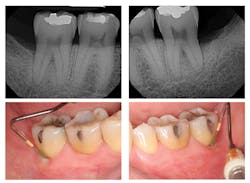

Figure 3: Three-year post-treatment radiographs

Evaluation-A six-month evaluation demonstrated reattachment (see Figure 2). The radiograph of tooth No. 18 exhibited 7.4 mm bone loss on the distal surface, reflecting an increased bone height of 4.4 mm. For tooth No. 31, the radiograph exhibited 6.2 mm bone loss, reflecting an increased bone height of 2.2 mm. Epithelial attachment gain was clinically evident as well (see Table 2). Pocket depths had marked improvement with elimination of furcation involvement on both teeth, decreased mobility of tooth No. 18, and no increase in recession. The patient also submitted three-year post-treatment radiographs taken by the dental hygienist of record (see Figure 3) with evidence of bone stability.